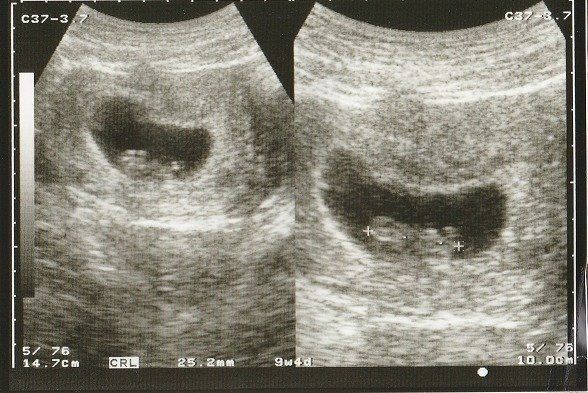

妊娠9週目のエコー写真 何となく人の形?

落花生のように真ん中がくびれた胎児の形が見えるようになってきました。

妊娠8週目のエコー写真 10mm以上に成長

CRL(頭殿長=頭からおしりまでの長さ)が10mmを超えました。

順調に大きくなっていますが、まだまだ「大丈夫だろうか?」という不安が大きかった時期。